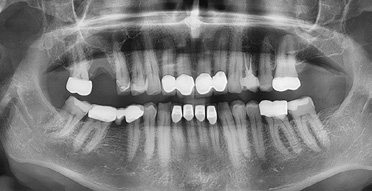

Wenn aufgrund der röntgenologischen Diagnostik klar ist, dass ich pulpennah exkavieren muss, lasse ich Carisolv einwirken und exkaviere dann mit dem PolyBur P1. Ich informiere den Patienten, dass eventuell eine Wurzelbehandlung folgen könnte, ich dies jedoch zu vermeiden versuche. Ist die Karies tatsächlich weit fortgeschritten, also tief im Dentin, kann es natürlich der Fall sein, dass ich mit PolyBur P1 die Pulpa eröffne.